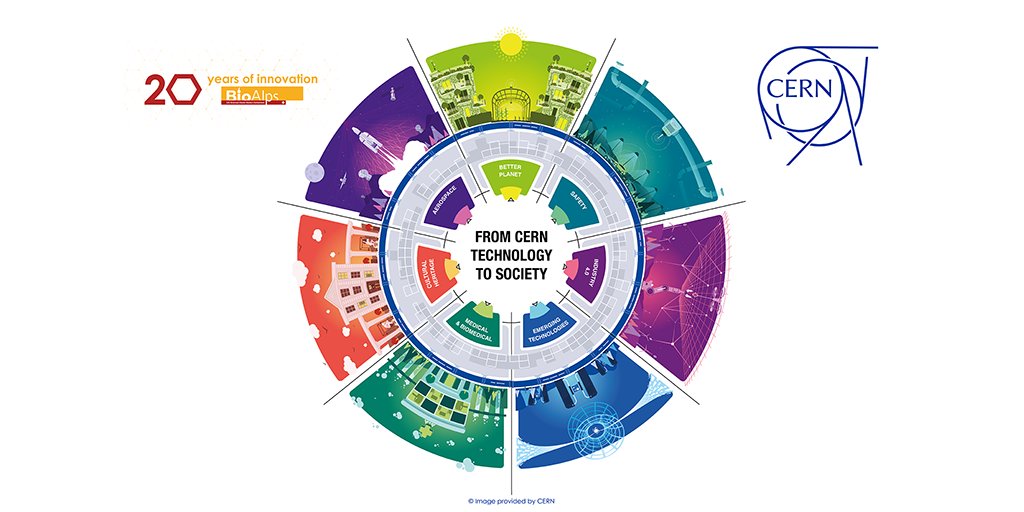

🏥 Discover #CERNImpact in medical imaging (1/5) ⚕️ After years of development in NZ 🇳🇿, MARS Bioimaging 3D colour X-ray scanner has arrived in Europe to start trials at CHUV / Centre hospitalier universitaire vaudois 🇨🇭 to get certified for medical use. #CERNKT Find out more: kt.cern/news/news/know…